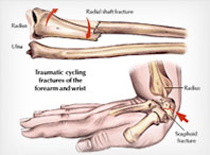

Fractures and sports Injuries

Children’s factures are different than Adult factures in many ways.